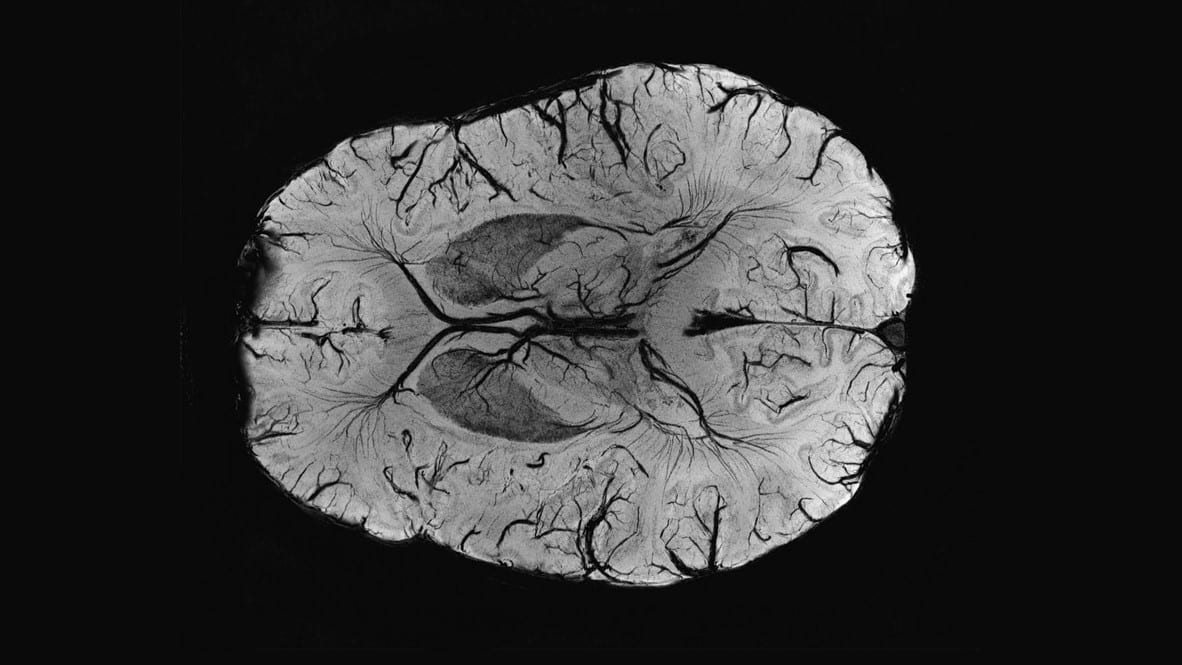

Все они влияют на формирование мозга и не проходят для него бесследно. Новая работа ученых из Университета Неймегена в Нидерландах показала, что такие факторы сказываются на размерах различных участков мозга и обнаруживаются даже во взрослом возрасте. Статья об этом опубликована в журнале Nature Neuroscience.

В возрасте 25 и 33 лет участники опыта проходили детальное сканирование головного мозга в томографе. Полученные данные ученые анализировали с помощью искусственного интеллекта, искавшего особенности анатомии, которые коррелировали с теми или иными прошлыми невзгодами. «Они проявились очень ясно, и такие корреляции оставались стабильны во времени. Мы находили их и в том, и в другом возрасте», — сказала Натали Хольц.

Например, в норме объем вентромедиальной орбитофронтальной коры (vmOFC) с возрастом понемногу уменьшается. Однако у людей, переживших разные стрессы в прошлом, этот процесс проходит иначе. Негативные психосоциальные события ускоряли уменьшение объема, а такие же события, но связанные с родами (например, преждевременное рождение), замедляли этот процесс. Подобные отклонения обнаружили и в областях лимбической системы, включая гиппокамп и миндалевидное тело.